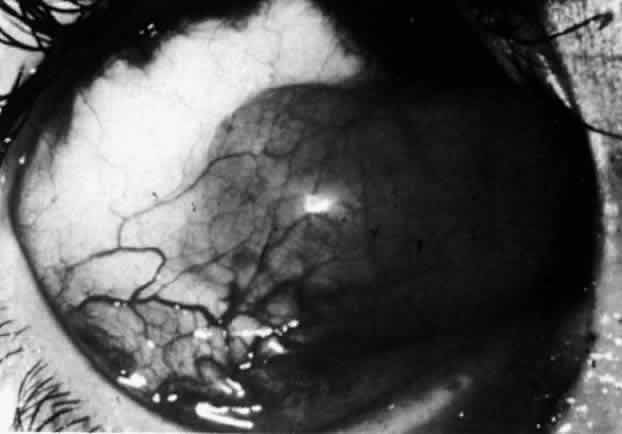

Nodular Anterior Scleritis

Although patients with nodular anterior scleritis resemble those with nodular episcleritis on cursory examination, detailed examination reveals marked differences. The nodule or nodules (they may be multiple) consist of scleral tissue that is immovable episclera is tightly adherent to the nodule, which is tender to the touch. Although the sclera sometimes becomes transparent below the nodule, it does not become necrotic, nor does the condition extend beyond the site of the nodule, as occurs in necrotizing scleral disease (Fig. 36).

(see Fig. 28; Figs. 34 and 35). The edematous

Fig. 34. Scleral edema has displaced all the vessel layers forward. Area surrounding the nodule is acutely inflamed.

Fig. 35. Multiple scleral nodules. Surrounding inflammation is deep and intense. (Watson PG: Management of scleritis. In: Recent Advances in Ophthalmology, Vol 5. London, Churchill-Livingstone, 1975)

The angiogram is similar to that of diffuse anterior scleritis (i.e., there is a rapid filling pattern and deep scleral leakage of dye).26